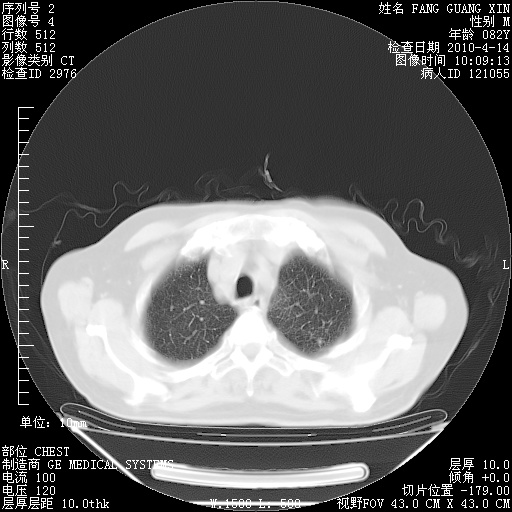

4月14日肺部CT

23.JPG

24.JPG

25.JPG

26.JPG

肺部CT平扫未见异常。